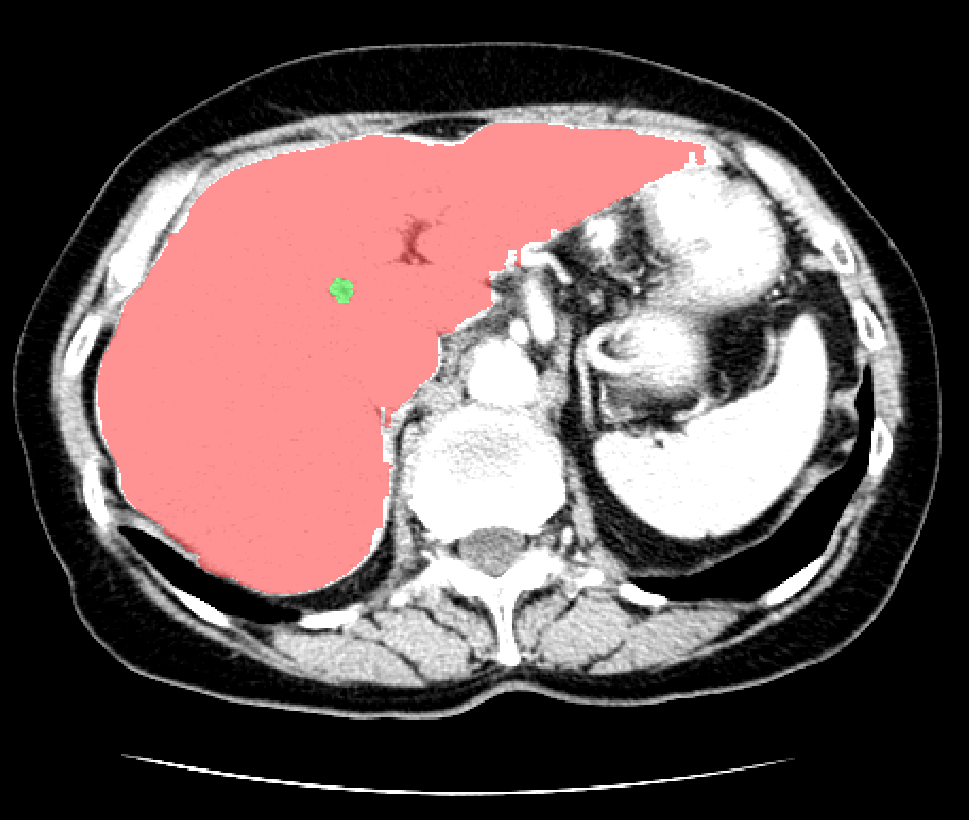

基于飞桨PaddlePaddle框架,我使用Res-Unet网络结构在 LiTS 数据集[2]上训练了一个分割网络,最终在肝脏和肝肿瘤上分别达到了 0.92 和 0.77 的分割准确率。LiTS数据集是目前最大的开源肝脏分割数据集,其中包含130名患者的CT扫描和医生对患者肝脏及肿瘤的分割标注,下图是数据集中的一个示例:

![]()

图1 肝脏分割示例